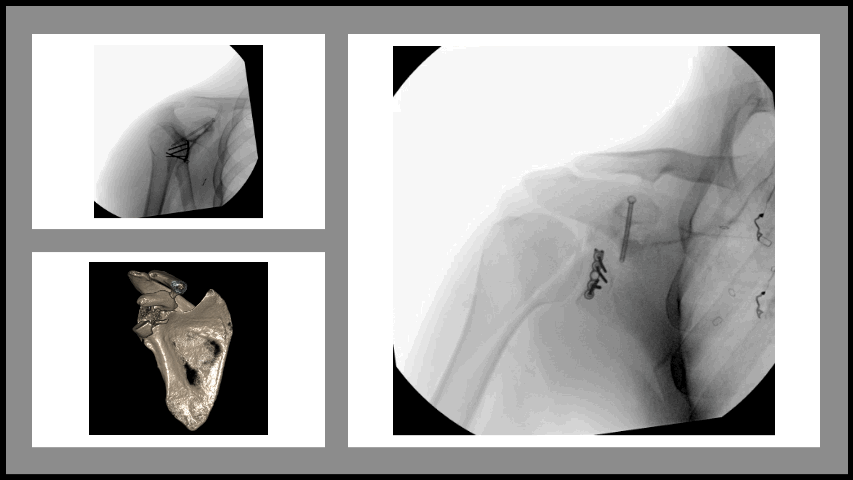

![]() Transverse patella fracture | ![]() Clavicle fracture | ![]() Glenoid and scapula fracture | ![]() Proximal humerus fracture |